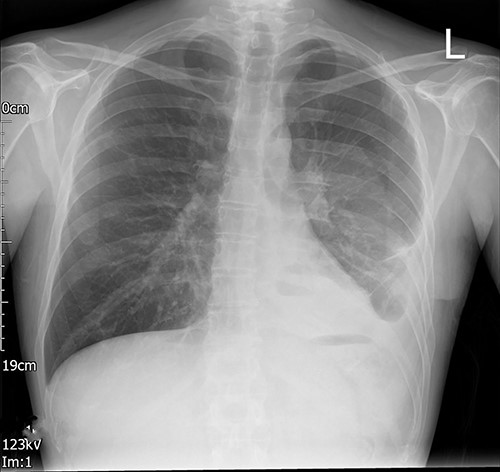

A young adult with a past medical history of asthma, depression and high alcohol intake was admitted with coronavirus (COVID) pneumonitis and type 2 respiratory failure. During his admission to the local hospital, he developed a left-sided pleural effusion. After confirming the diagnosis by a CT scan, an 18 French gauge (Fr) chest drain was inserted by the Seldinger technique (Fig. 1). The never event of a retained foreign body intrapleural was brought to light at the post-procedure X-ray (Fig. 2). The X-ray showed the retention of the guidewire in the thoracic cavity. The patient was referred to us for urgent retrieval of the guidewire. The patient was transferred, and a course of intravenous antibiotics for 10 days was completed, as per the advice of the infectious diseases colleagues; once the infection parameters were normal and the patient was COVID-19 negative, he underwent a left-sided video-assisted thoracoscopic surgery (VATS) for removal of the foreign body.

Posterior–anterior chest radiograph after chest drain insertion showing the retained guidewire in the left pleural cavity. In addition, left pleural effusion can be noted.